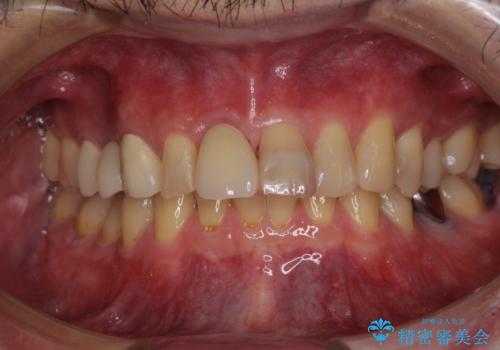

- 前歯の被せものが脱離したとのことで来院された患者様です。

診察の結果、前歯が縦に破折しており、抜歯が必要と診断されました。

補綴治療としては、インプラントあるいはブリッジの2つがありますが、患者様と相談した結果、インプラントによる補綴治療を選択することとなりました。